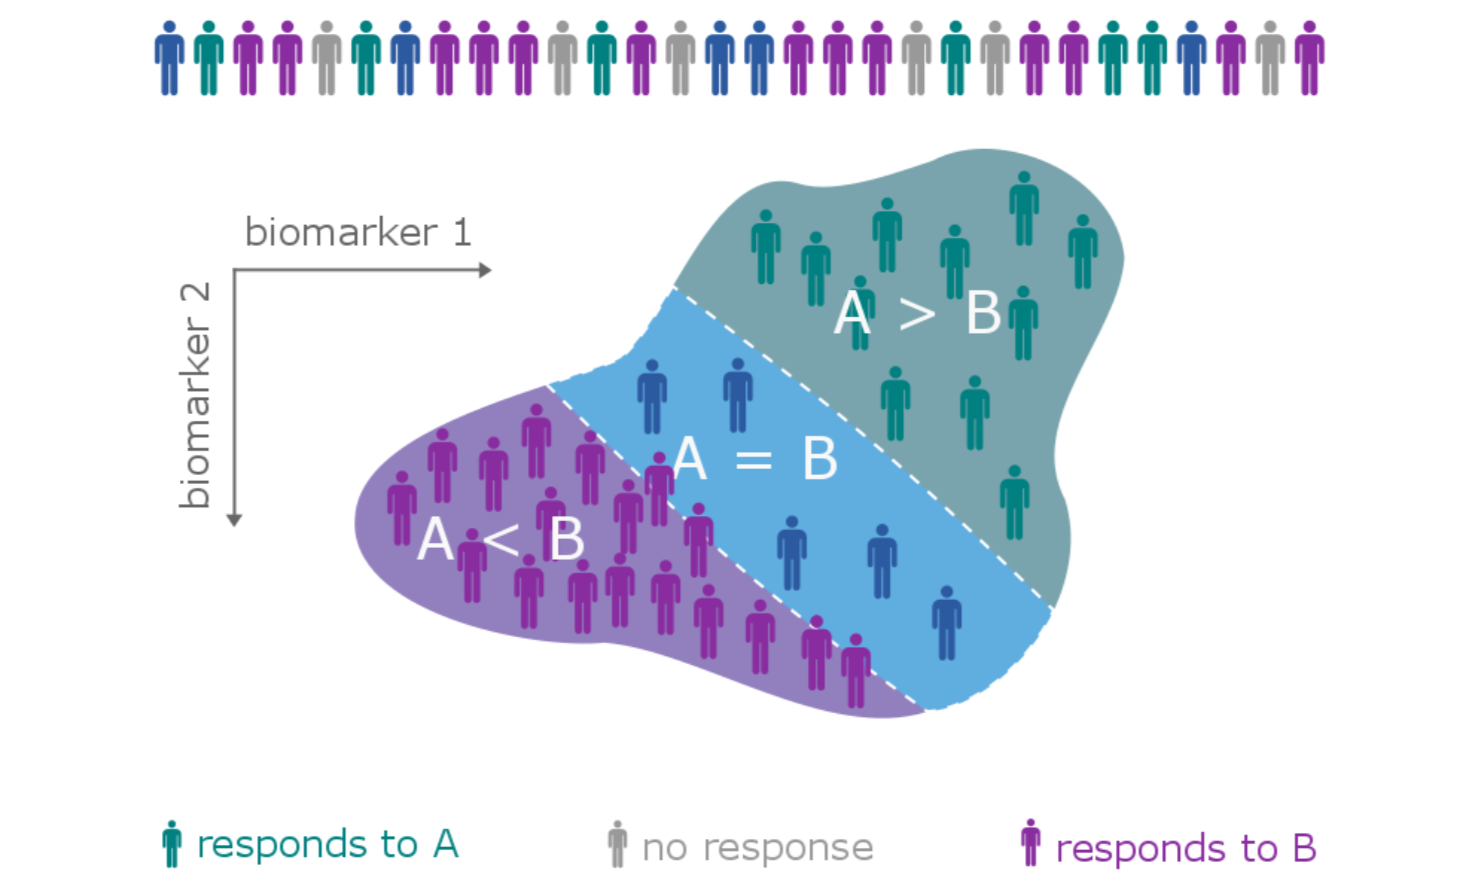

The patient heterogeneity problem

The patient heterogeneity problem

The patient heterogeneity problem

Hobbs, Kane, Hong, and Landin. Statistical challenges posed by basket trials: sensitivity analysis of the Vemurafinib study. Accepted to the Annals of Oncology.

A subtype is a group of patients with similar, measurable characteristics who respond similarly to a therapy.